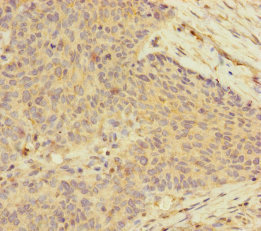

圖片:

應(yīng)用范圍:ELISA, IHC

Application Recommended Dilution IHC 1:20-1:200 -